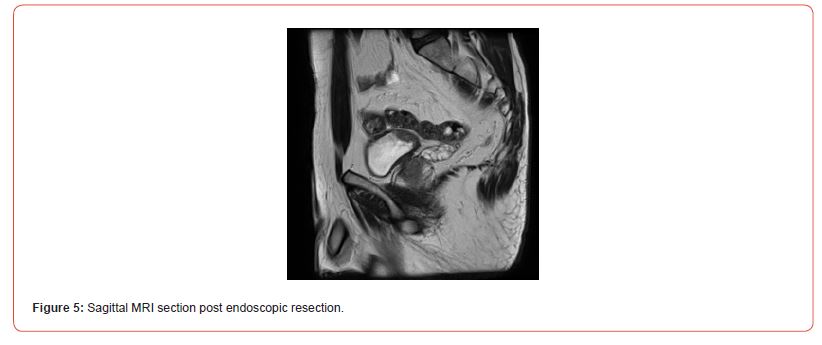

Immunostaining of the tumor cells showed heterogeneous positivity for keratin AE1E3. This positivity was lower in terms of intensity compared to the adjacent normal urothelial lining. There was no positivity for anti-p63 antibody. The tumor cells were focally positive for anti- Desmin and SMA antibodies. The proliferation index, evaluated using anti-Ki67 antibody, was estimated to be between 5 and 10% depending on the analyzed areas. There was strong and diffuse immunostaining for anti- ALK antibody. Fluorescence In Situ Hybridization (FISH) analysis showed rearrangement of the ALK gene in 84% of cells (Figure 3). The microscopic and immunohistochemical examinations are suggestive of IMT or pseudosarcomatous IMT. Microsatellite instability testing was performed. The MLH1, PMS2, MSH2, and MSH6 antibodies showed nuclear positivity, which is not suggestive of microsatellite instability for this tumor. A postoperative pelvic MRI (Figures 4&5) showed a heterogeneous enhancing lesion on the left postero-lateral wall of the bladder, measuring 26 x 22 x 14 mm, near the uretero-vesical junction, without extravesical extension.